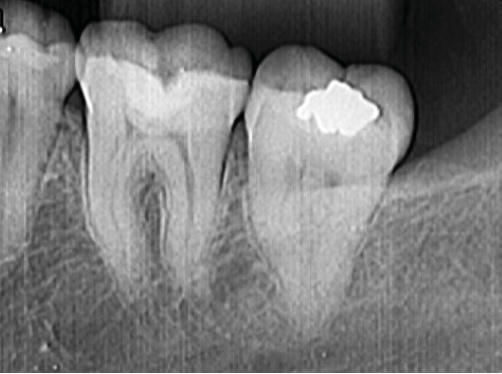

After checking occlusion with articulating paper and setting with a fine-grained diamond bur, the occlusal contacts were adjusted using a polishing cup (Figure 4). After the end of the restorative procedures, the patient was instructed about what foods to avoid in the first 24 hours and was asked to return for evaluation. In the first two weeks, the patient reported a reduction in pain, but it did not disappear. A month later, pain was mild and only felt when the patient had cold or hot foods. At that time, the patient was examined, and occlusion was once again evaluated and adjusted, and the restoration underwent finishing and polishing. Monitoring after that revealed a reduction of symptoms. After seven years, the patient reported no pain. The clinical examination revealed that the restoration remained satisfactory and there were no stains or infiltrations signs (Figura 5) The monitoring radiograph ruled out periodontal lesions or periapical pathologies (Figure 6).